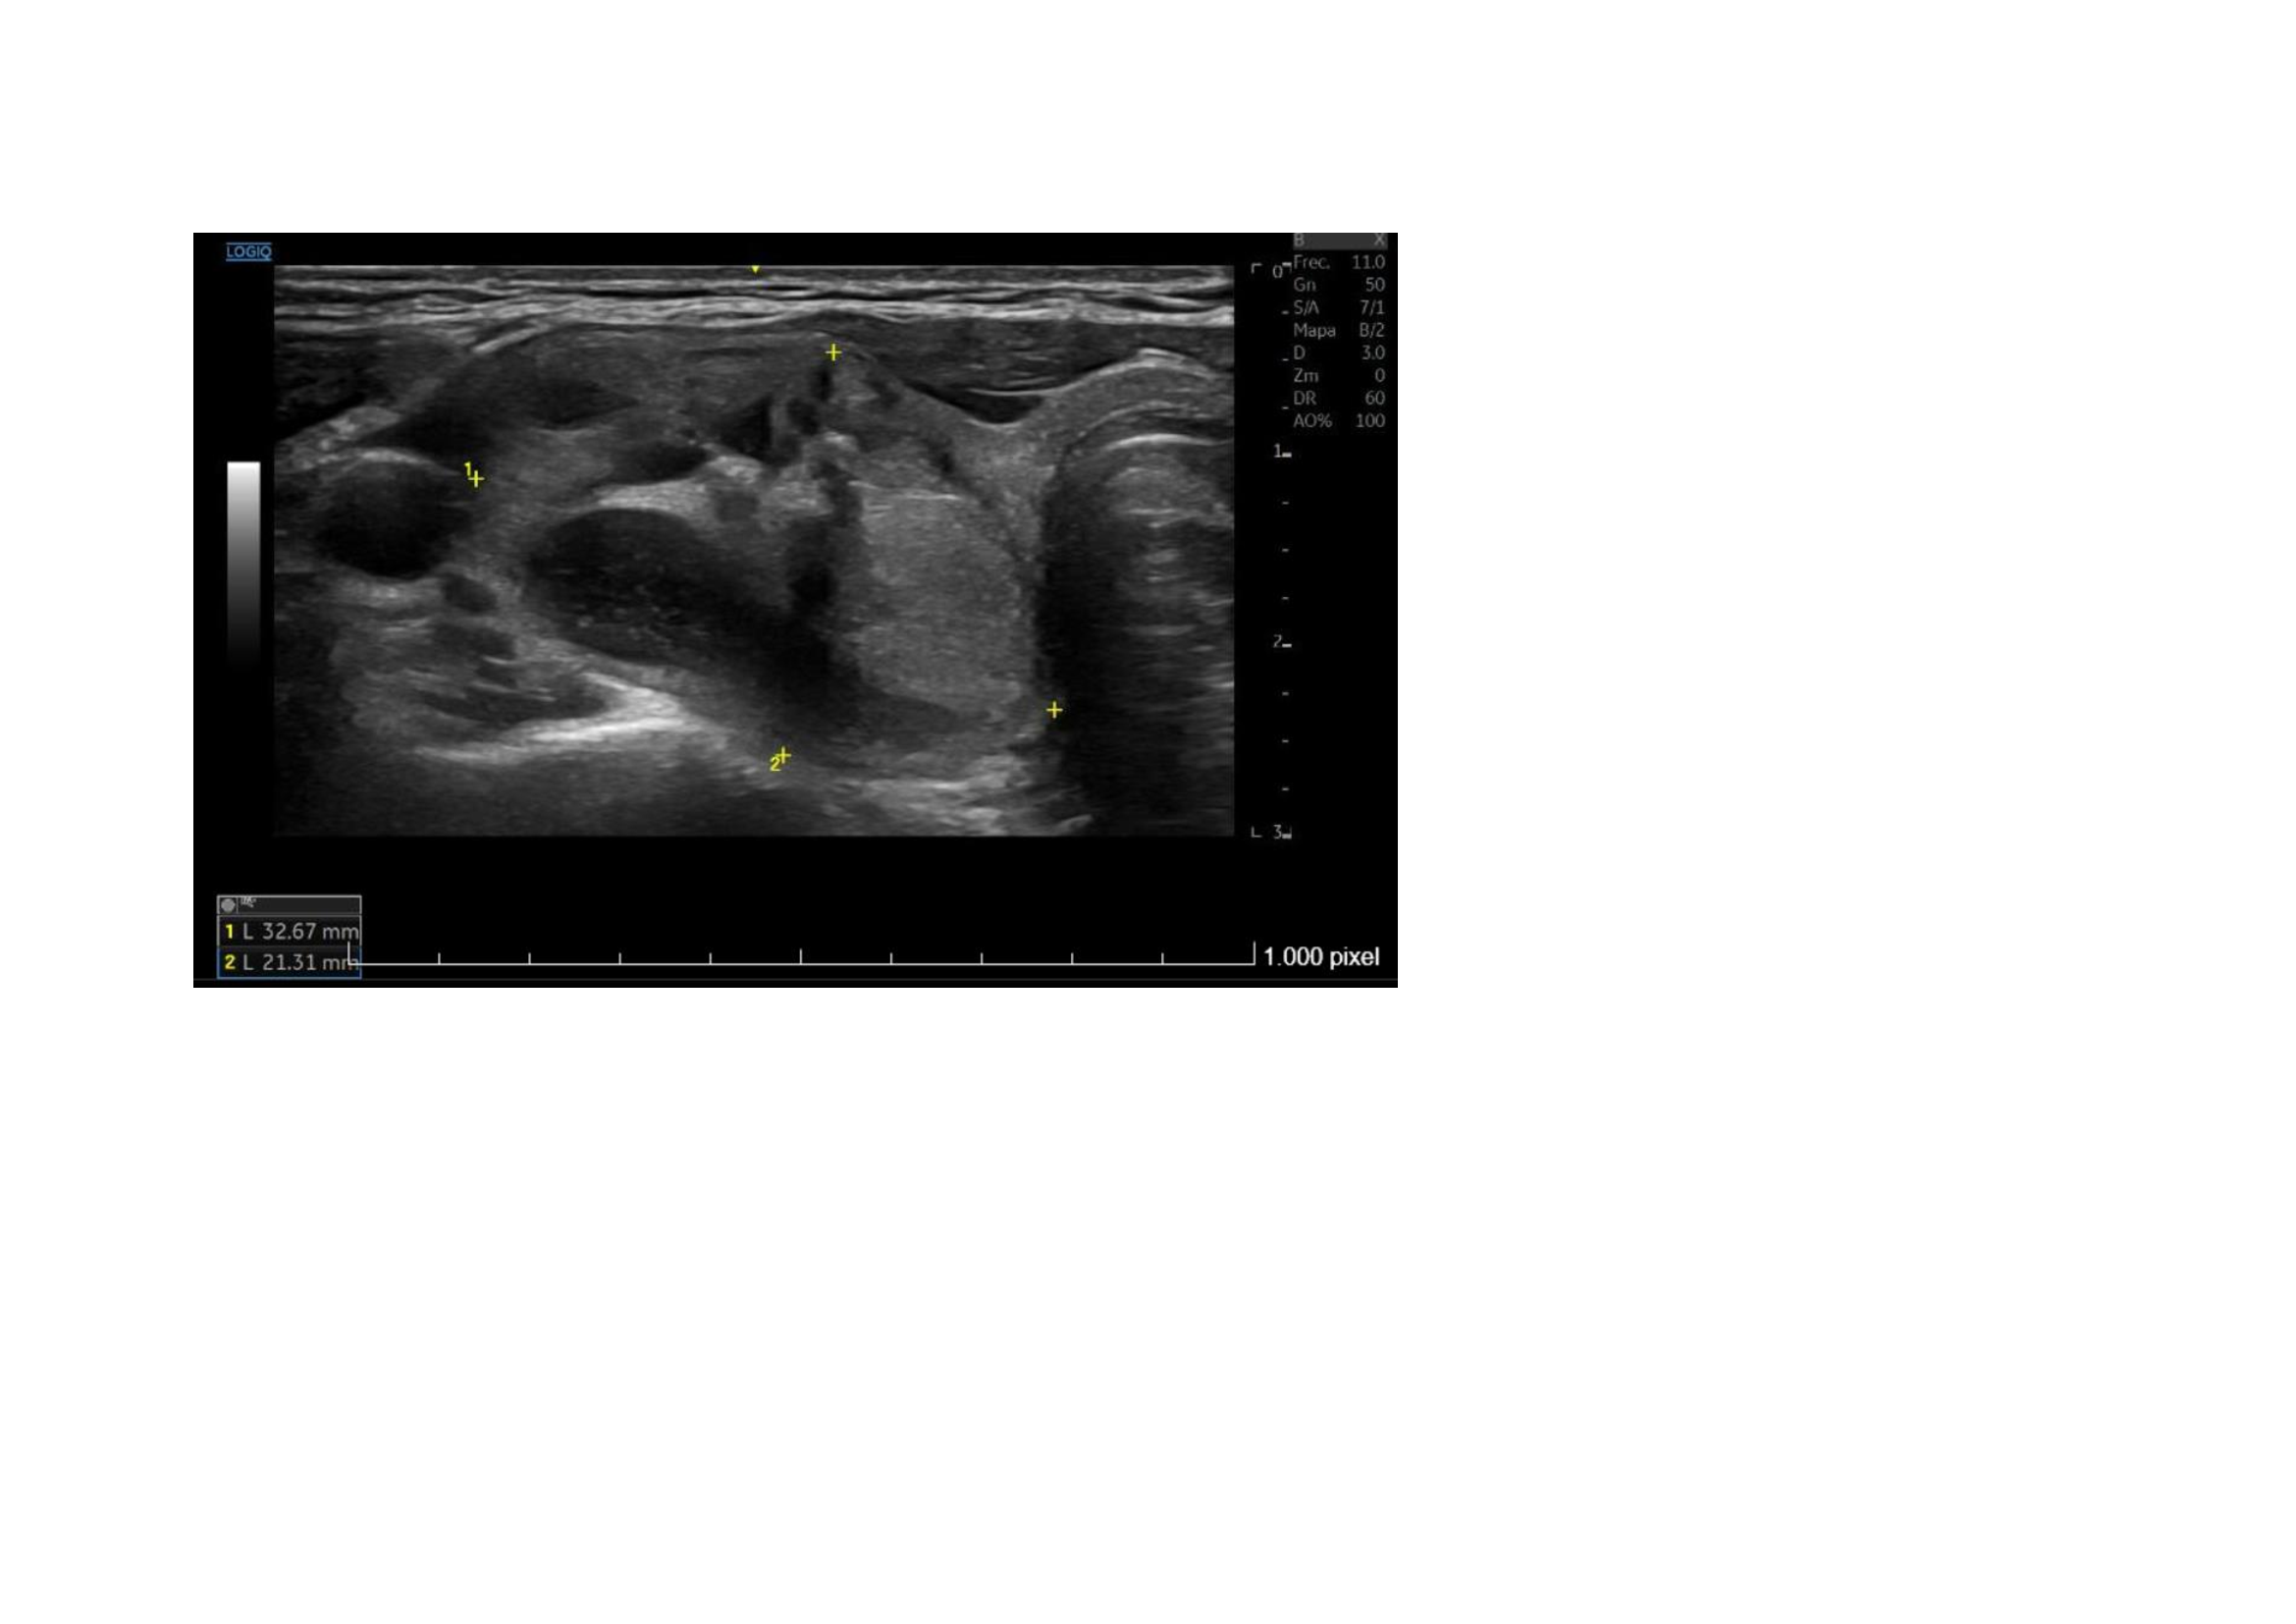

Ecografía clínica: En lóbulo tiroideo derecho observamos nódulo mixto sólido-quístico, de 11,8 x 14,5 x 15,4 mm, de bordes bien delimitados mayoritariamente hipoecogénico, parcialmente tabicado a nivel inferomedial, más alto que ancho con micro calcificaciones en su interior. TIRADS 5.

Ecografía Hospital: Lóbulo tiroideo derecho aumentado de tamaño (2,2 cm de diámetro anteroposteior), por la presencia de un nódulo sólido, heterogéneo, levemente hipoecoico, bien definido, con áreas de degeneración quística y calcificaciones groseras en su interior, de 22 x 21 x 33 mm. Resto del tiroides sin alteraciones. No se aprecian adenopatías cervicales. Glándulas salivares sin alteraciones. Conclusión: Nódulo en lóbulo tiroideo derecho, único, TIRADS 4.